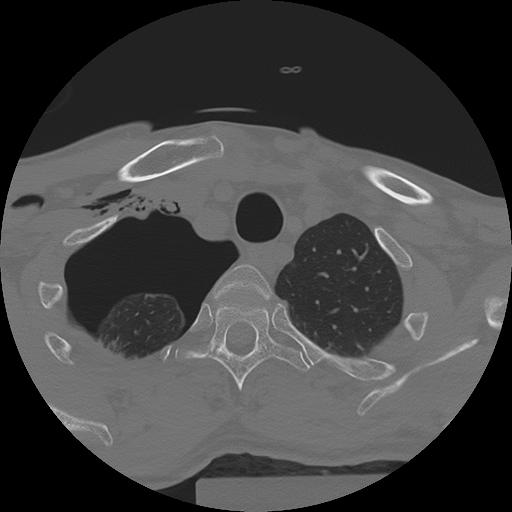

11 HUESO,,Axial,2.0,HUESO,,